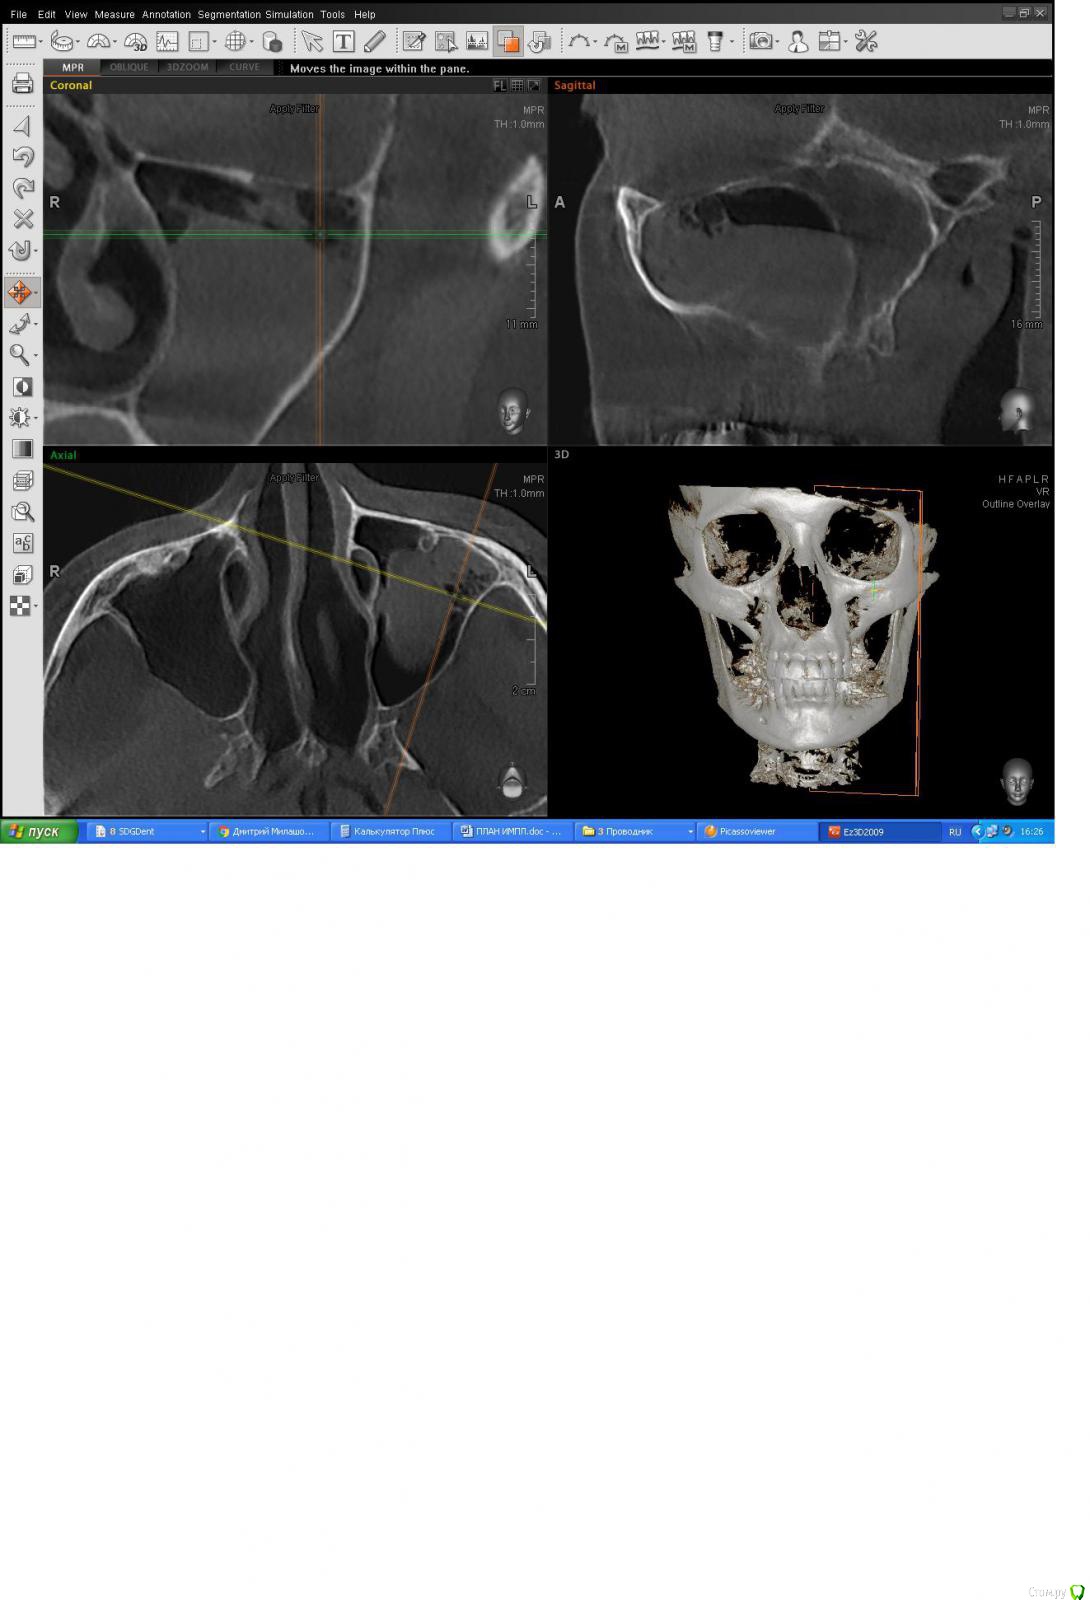

DoktorDre Опубликовано 15 марта, 2017 Поделиться Опубликовано 15 марта, 2017 Здравствуйте Коллеги.в области 25.27 планируется имплантация+ синус лифтинг.решил осмотреть соустье_оно открыто.смущает образование , на весь синус 2 квандранта , а так же пузыри воздуха на верху, как гроздья винограда.Лор не рекомендует делать синус.делать или нет ? Что это? Аспергиллы? Ссылка на комментарий

колесников Опубликовано 15 марта, 2017 Поделиться Опубликовано 15 марта, 2017 Пузырьки это газы. В пазухе уровень жидкости . Судя по всему-гнойный гайморит Ссылка на комментарий

Bier Опубликовано 15 марта, 2017 Поделиться Опубликовано 15 марта, 2017 на уровень жидкости не похоже. Пусть ЛОР сделает FESS Ссылка на комментарий

DoktorDre Опубликовано 15 марта, 2017 Автор Поделиться Опубликовано 15 марта, 2017 Нет это не жидкость точно. И с её слов это давно. Кт делала ранее. То есть делать синус рискованно? Ссылка на комментарий

колесников Опубликовано 15 марта, 2017 Поделиться Опубликовано 15 марта, 2017 Ну явно там процессы брожения идут и обычно они происходят в жидкой среде. Вероятно там и киста имеется (на коронарном срезе округлые контуры прослеживаются). Однозначно делать синус только после санации пазухи Ссылка на комментарий

DoktorDre Опубликовано 16 марта, 2017 Автор Поделиться Опубликовано 16 марта, 2017 Спасибо, коллеги. То есть там есть жидкость, по- любому,и это не просто полип. Да, я видел удаление таких кист,( Чиапаско?) но наверное браться не буду, т.к сам не делал. кстати, она легко отделаться от шнайдеровой? Ссылка на комментарий